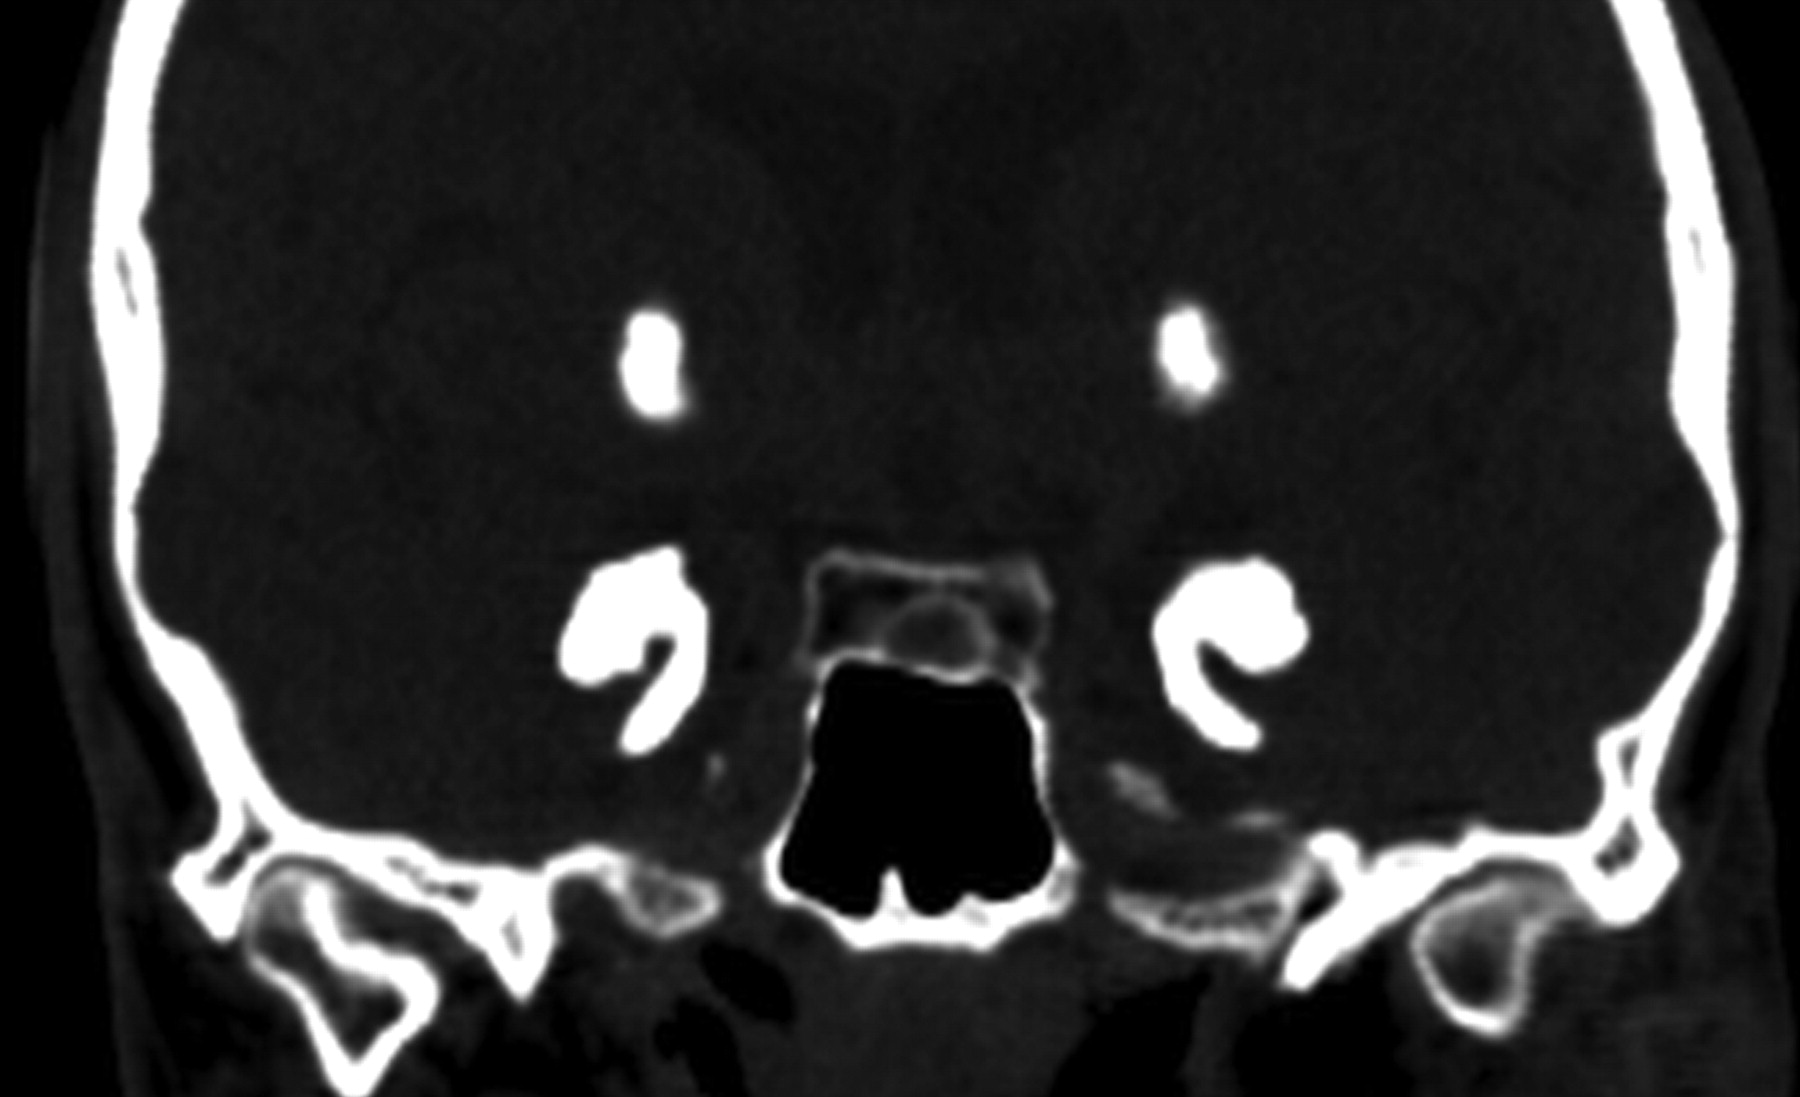

On CT, there were signs of bilateral symmetric amygdaloid and striatum calcifications without mass effect (Fig 2). On T2-weighted images, there were marked hypointense lesions in the mesial temporal lobes immediately anterior to the temporal horns and rounded bilateral striatal lesions (Fig 3). An incidental finding of parotid gland T2 hyperintensity was positively correlated with a history of left parotid gland recurrent inflammation.

Patient 1. Coronal CT reformatted image shows symmetric bilateral striatal, uncal, and amygdaloid calcifications.